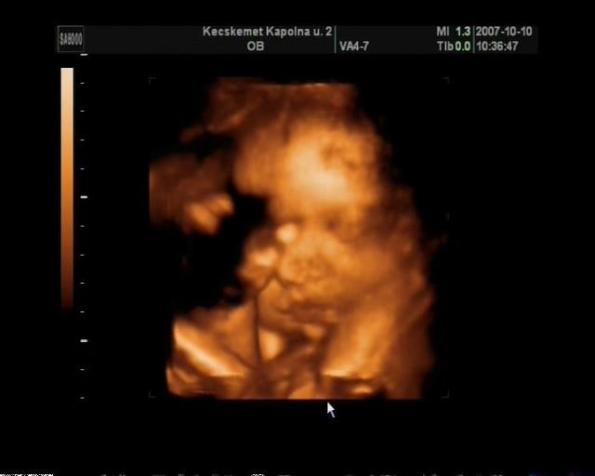

Voltunk 5 hete 4 D ultrahangon mellékelek egy képet remélem nem baj :D

Kép

Nagy Bálint Levente a pici kisfiam :D

Irigyellek a SOTE-s szülésért :wink: Gratula Leventéhez! Nagyon szép baba, s nagyon jó a felvétel!!!! A párod is tündéri lehet, az alapján a pár sor alapján, amit írtál!